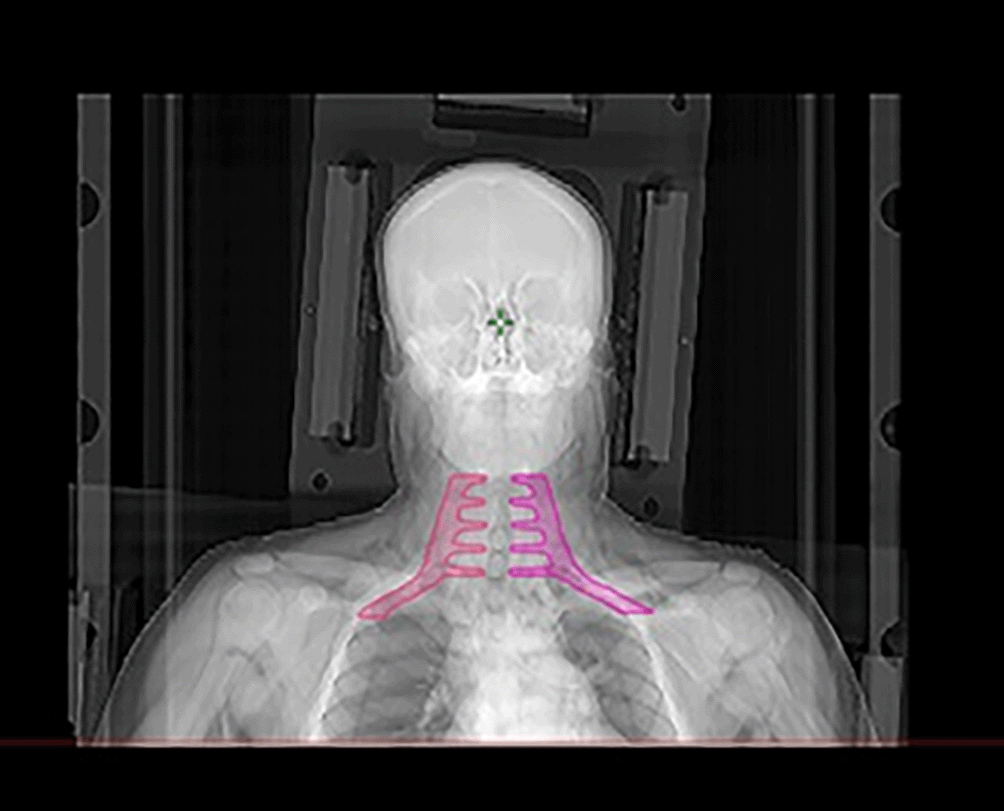

Imaging for treatment planning was conducted using a Philips® BigBore simulator scanner with 3 mm slice thickness. Patients were positioned supine, immobilized with a 5-point thermoplastic mask, and underwent a dosimetric scan with intravenous contrast when there were no contraindications. Target volumes were defined according to ICRU guidelines,14,15 with three key volumes: Gross Tumor Volume (GTV), Clinical Target Volume (CTV), and Planning Target Volume (PTV) (Figure 1). The GTV includes visible tumor, the CTV encompasses areas with potential microscopic disease, and the PTV adds a margin to account for uncertainties such as patient motion and setup errors. High-risk CTVs receive the highest dose, extending from the GTV to include the nasopharyngeal region, with margins depending on anatomical boundaries and nodal involvement.16,17 Intermediate- and low-risk CTVs are defined based on the tumor’s extension and regional lymph node involvement. The PTV was defined by extending the CTV by 5 mm in all directions to account for treatment uncertainties. This margin was applied to both the nasopharyngeal and lymph node regions (Figure 1). In our study, the brachial plexus was delineated following the Radiation Therapy Oncology Group (RTOG 618) guidelines, with contouring adjustments at the lower part based on the recommendations of Sun Ki Yi et al. This adjustment was necessary due to the requirement to irradiate the level 4 lymph node area within the prophylactic volume18,19 (Figure 2). The treatment was administered using a linear accelerator with the IMRT technique (VARIAN CLINAC® IX, MLC 120) and 6 MV X-rays (Figure 3). All patients received 2 Gy per session, five days a week, targeting the tumor volume and affected lymph nodes, totaling 70 Gy. For intermediate-risk cervical lymph node areas (retropharyngeal, II, III, V, and occasionally IV, Ia, Ib according to N involvement), the prescribed dose was 59.4 Gy with 1.7 Gy per fraction across 35 sessions in simultaneous integrated boost.

25d45b26-5387-42c6-94b5-f7b7a30f5503_figure2.gif

Figure 2. Digital delineation of the brachial plexus.